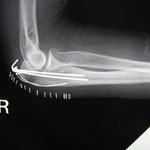

○肘頭骨折

肘を着いて転倒 超音波検査で骨折が確認できたので病院を紹介しました。

肘の頭と書きますが、ここが折れると手術摘要です。筋肉の影響で骨折した部分が離れようとするからです。

手術後は当院に通ってもらい肘に超音波をかけました。超音波の微量な刺激を骨折部分に当てると骨の癒合が早まると見直されています。 同時に温熱療法 マッサージも施しました。予後は大変良かったです。